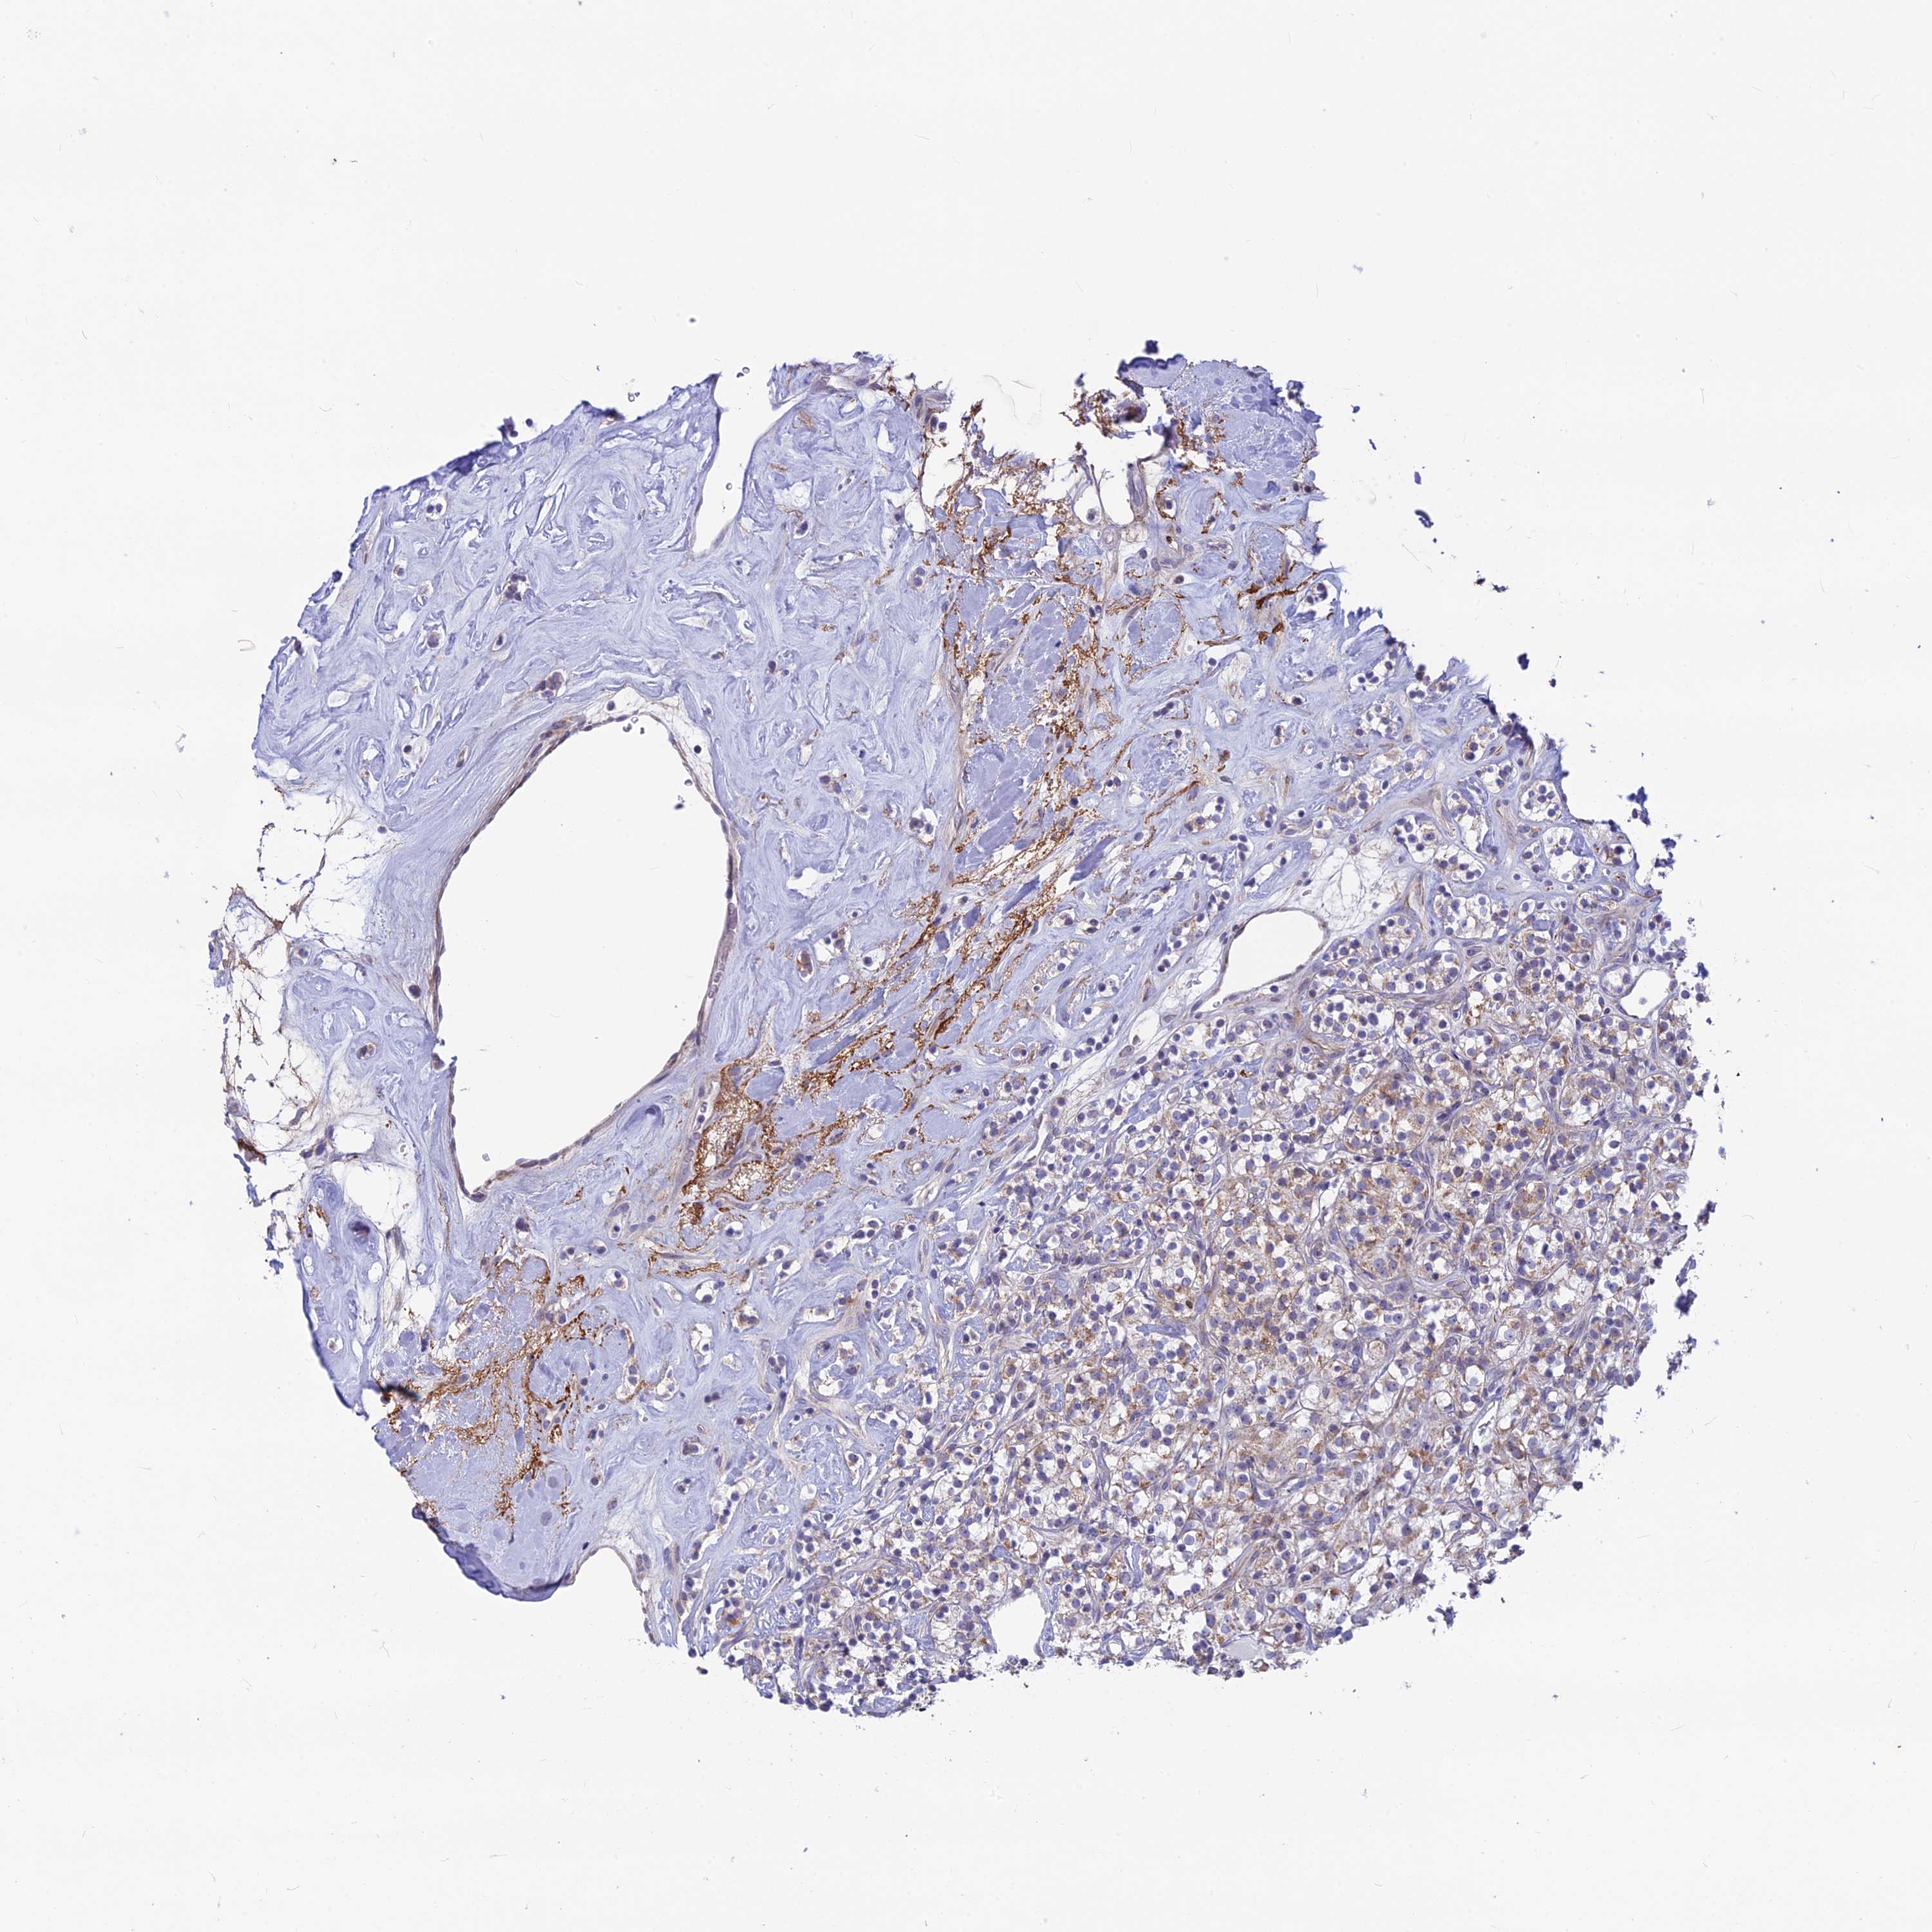

KIDNEY RENAL CLEAR CELL CARCINOMA (VALIDATION) - Interactive survival scatter ploti

The Survival Scatter plot shows the clinical status (i.e. dead or alive) for all individuals in the patient cohort, based on the same data that underlies the corresponding Kaplan-Meier plots. Patients that are alive at last time for follow-up are shown in blue and patients who have died during the study are shown in red.

The x-axis shows the expression levels (FPKM) of the investigated gene in the tumor tissue at the time of diagnosis. The y-axis shows the follow-up time after diagnosis (years). Both axes are complimented with kernel density curves demonstrating the data density over the axes. The top density plot shows the expression levels (FPKM) distribution among dead (red) and alive patients (blue). The right density plot shows the data density of the survived years of dead patients with high and low expression levels respectively, stratified using the cutoff indicated by the vertical dashed line through the Survival Scatter plot. This cutoff is automatically defined based on the FPKM cutoff that minimizes the p-score. The cutoff can be changed by dragging the vertical line or by entering a cutoff value in the square labeled "Current cut-off".

Under the Survival Scatter plot the p-score landscape (black curve; left axis) is shown together with dead median separation (red curve; right axis). Dead median separation is the difference in median mRNA expression between patients who have died with high and low expression, respectively. It is calculated as follows: median FPKM expression of dead patients with high expression - median FPKM expression of dead patients with low expression. This is intended to aid the user in visually exploring custom cutoffs and the associated p-scores and dead median separation.

Individual patient data is displayed and can be filtered by clicking on one or more of the category buttons on the top of the page. Categories describing expression level and patient information include: high, low, alive, dead, female, male and tumor stages. The scale of the x-axis can be toggled between linear and log-scale by clicking on the "x log" button. Mouse-over function shows TCGA ID, patient information and mRNA expression (FPKM) for each patient.

& Survival analysisi

Kaplan-Meier plots summarize results from analysis of correlation between mRNA expression level and patient survival. Patients were divided based on level of expression into one of the two groups "low" (under cut off) or "high" (over cut off). X-axis shows time for survival (years) and y-axis shows the probability of survival, where 1.0 corresponds to 100 percent.

PLAC9 is potential prognostic, high expression is favorable in Kidney Renal Clear Cell Carcinoma (validation)

Best expression cut offi

Based on the FPKM value of each gene, patients were classified into two groups and association between prognosis (survival) and gene expression (FPKM) was examined. The best expression cut-off refers the FPKM value that yields maximal difference with regard to survival between the two groups at the lowest log-rank P-value. Best expression cut-off was selected based on survival analysis .

When clicking on this number, the vertical dashed line indicating cut-off, the interactive survival plot, and the Kaplan-Meier curve will be adjusted to show results based on the best expression cut-off.

: 7.53

P scorei

Log-rank P value for Kaplan-Meier plot showing results from analysis of correlation between mRNA expression level and patient survival.

N/A

TCGA RNA samplesi

RNA-seq data is reported as average FPKM (number Fragments Per Kilobase of exon per Million reads), generated by the The Cancer Genome Atlas (TCGA) .

Normal distribution across the dataset is visualized with box plots, shown as median and 25th and 75th percentiles. Points are displayed as outliers if they are above or below 1.5 times the interquartile range. FPKM values of the individual samples are presented next to the box plot.

Average pTPM 18.3

Number of samples 100